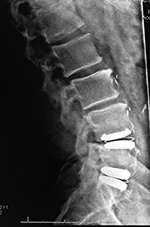

Metal-on-polyethylene total disk replacement at L4-5 and L5-S1 |

| Lumbar spine fusion and metal-on-polyethylene disk replacement at L4-5 and L5-S1 |

| 31 year-old man with chronic low back pain. In addition to the total disk replacements at L4-5 and L5-S1 there is also a laminectomy from L4 to S1 with posterolateral bony fusion masses and pedicle screws with connecting rods on each side. |